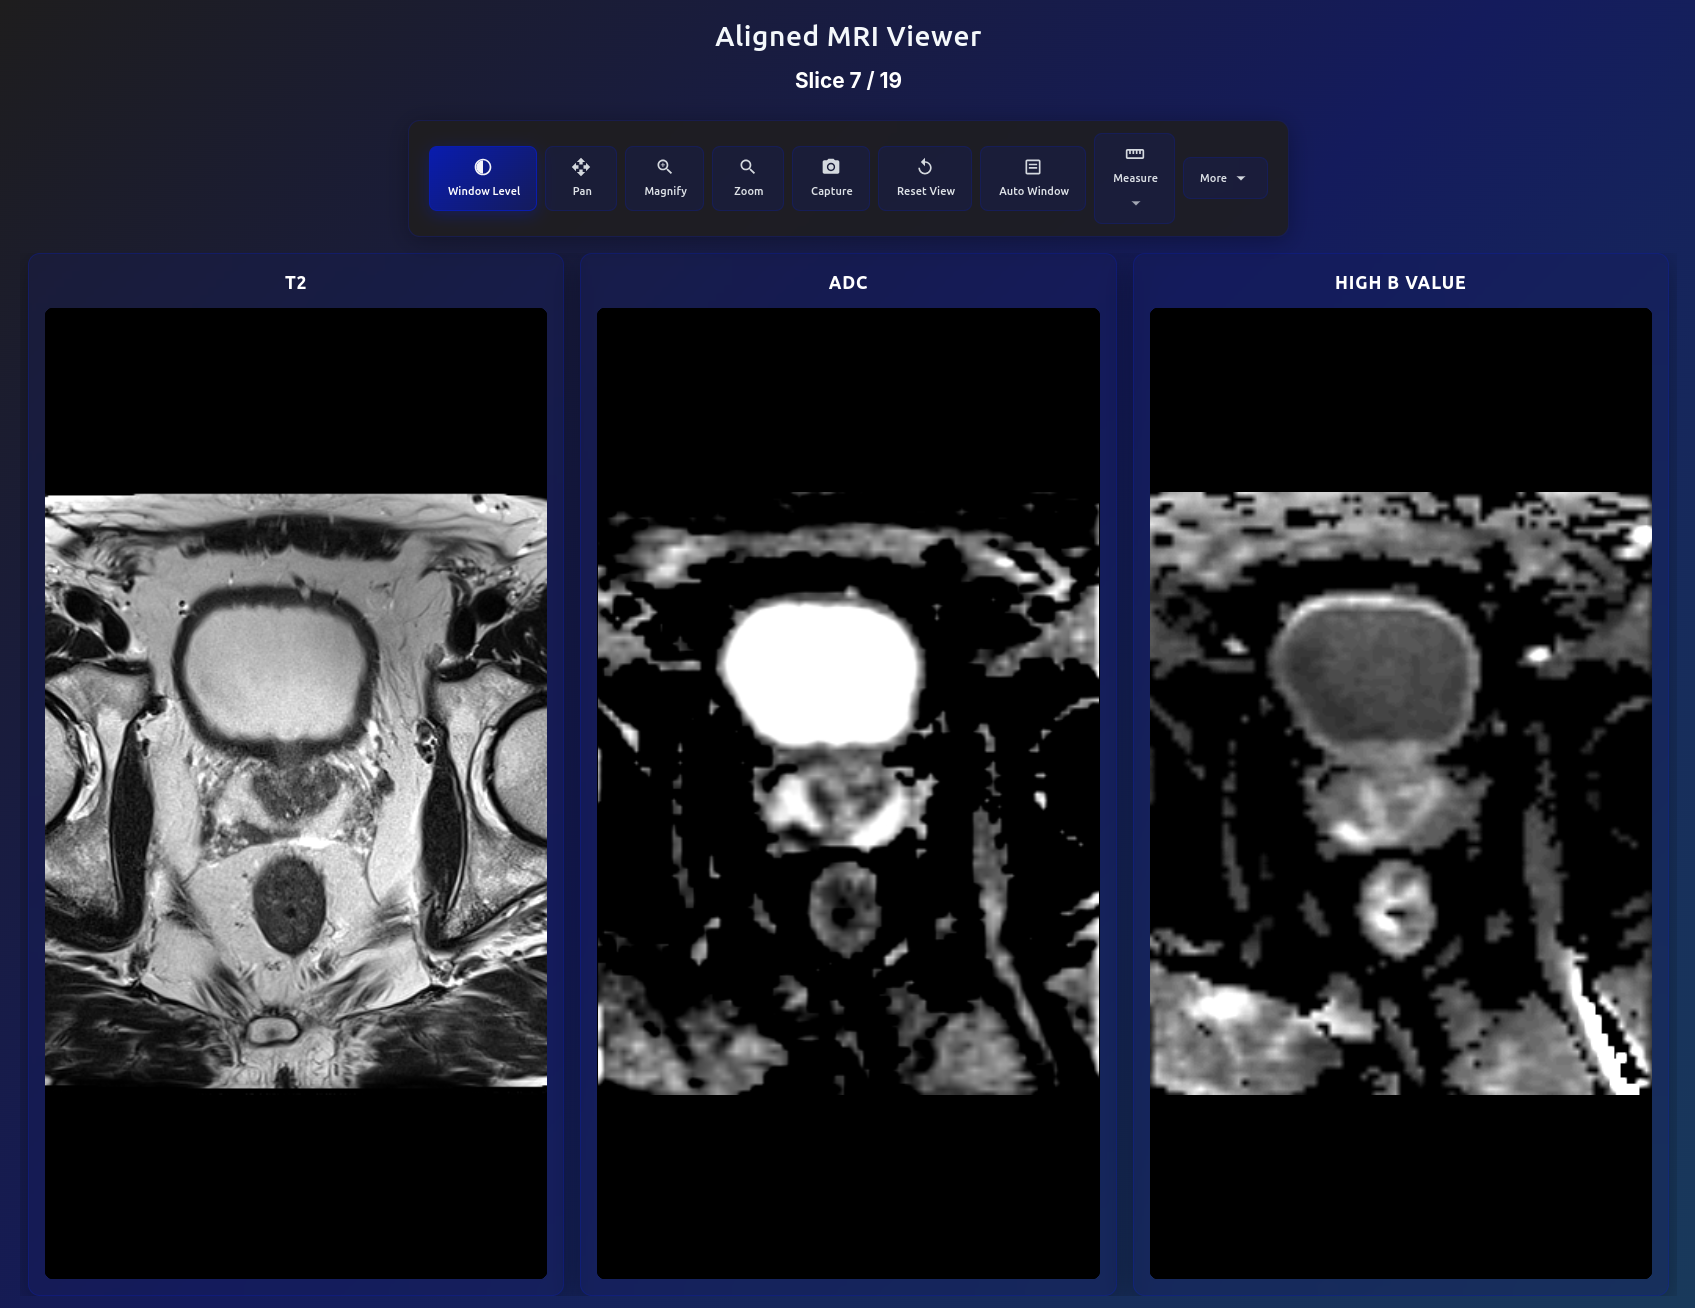

Aligned MRI viewer showing T2, ADC, and High B Value in same voxel space

Automated Image Alignment

All biparametric series (T2, ADC, high b-value) are automatically registered into the same voxel space using affine alignment. Scroll through any slice and all three sequences stay perfectly synchronized — enabling direct visual comparison of signal characteristics across modalities.